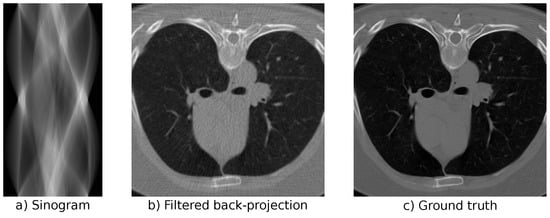

3.2. Computed Tomography

4.2. Computed Tomography